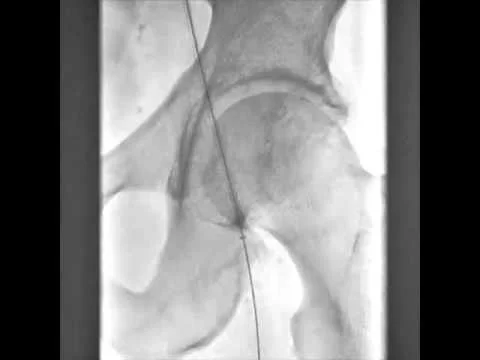

BTK CTO Viance & Enteer